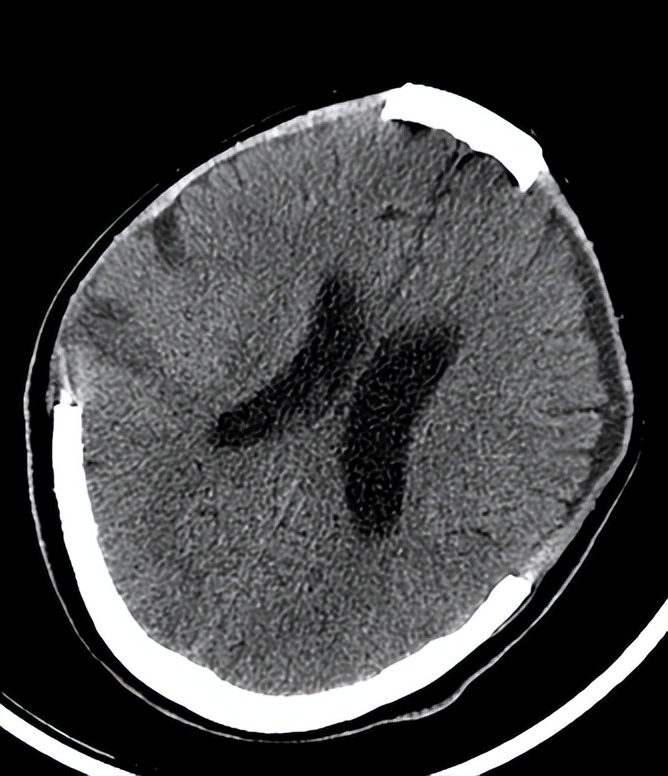

06-20复查头CT

6.23 患者已经服完一个疗程中药。

结合西医一系列治疗措施,患者意识状态开始 由昏迷转入昏睡状 ,气管套管内的痰明显减少,无呼吸困难。

神志昏睡状,GCS评分8T分(E4MTV4)双侧瞳孔3.0mm,对光反射灵敏。骨窗张力不高。双肺呼吸音清,下肺闻及散在湿罗音。四肢肌力检查不配合,左侧肢体未见肌肉收缩,双侧巴氏征阳性。此时我不在现场,科主任给我发了6月20日的头颅CT,和患者当时的病情描述,并拍了患者的照片发送给我。我考虑患者受到如此严重的颅脑创伤,身体元气大伤,如果不及时补益,即使生命保住,很可能留下严重后遗症。